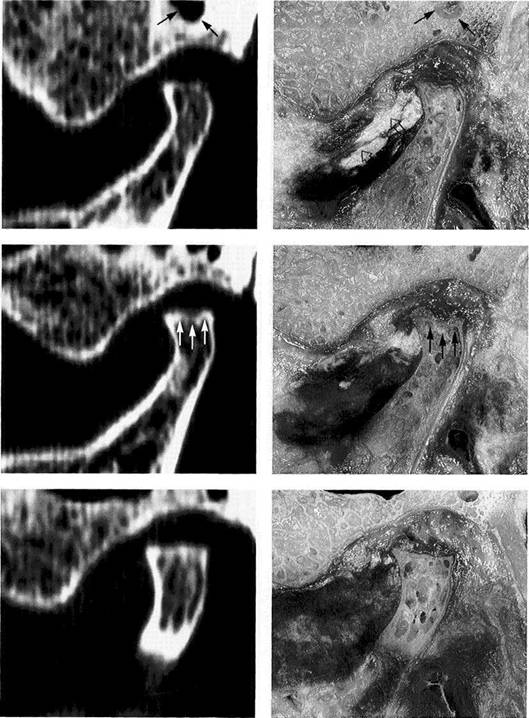

Computed Tomography of the Temporomandibular Joint and its Anatomical Correlation

CT is especially suited for representing the morphology of bone (Thompson et al. 1984, Westesson et al. 1987, Tanimoto et al. 1990, de Bont et al. 1993, Hu and Schneiderman 1995). Therefore, it is also employed for evaluating therapeutic measures (Fernandez Sanroman et al. 1998, Kawamata et al. 1998) and for planning implant procedures (Westesson 1996, Kraut 1998). However, on small structures with a high degree of curvature, such as the condyle and fossa, the so-called partial volume effect can cause one to overestimate the thickness of the cortical bone by as much as 200% (Ahlqvist and Isberg 1998). For investigating the disk, CT is

not the method of choice (de Bont et al. 1993, van der Kuijl et al. 1994). The sensitivity of disk diagnostics with CT scans is 0.86, but because the disk is often confused with the ten­don of the lateral pterygoid muscle, specificity is only 0.5. An elevated adsorption of radiation by the disk does provide evidence of hyalinization, calcification, and metaplasia (Paz et al. 1990). Remodeling processes in response to orthodon­tic treatment are seen as double contours of cortical bone in the fossa and on the condyle (Paulsen 1995).

Lateral portion of the joint

A computed tomogram and a macroscopic anatomical prepara­tion of the lateral portion of a human temporomandibular joint. Left: Because the CT machine was not fitted with a soft-tissue win­dow, the soft tissues cannot be identified. The low thickness of the slice causes some of the marrow spaces to appear as cavities (ar­rows).

Right: Because in this specimen the insertion of the lateral pterygoid muscle lies farther lateral than usual, part of the tendon (outlined arrows) can be recognized.

Central portion of the joint

Pictures of the central portion of the same joint. Notice the precision with which the CT reproduces the contours of the osseous structures (arrows).

Medial portion of the joint

In addition to the contours of the fossa and protuberance, the cancel­lous bone of the condyle is promi­nently reproduced in the medial slice of the joint as well. The ability of CT to accurately reproduce the bony articular surfaces should not mislead one into thinking that CTs are absolutely necessary for all tem­poromandibular joint problems. They are practical for joint deforma­tions associated with syndromes, fractures, ankylosis, or tumors, but all other joint surface lesions can be adequately diagnosed through other clinical procedures (see also p. 68).